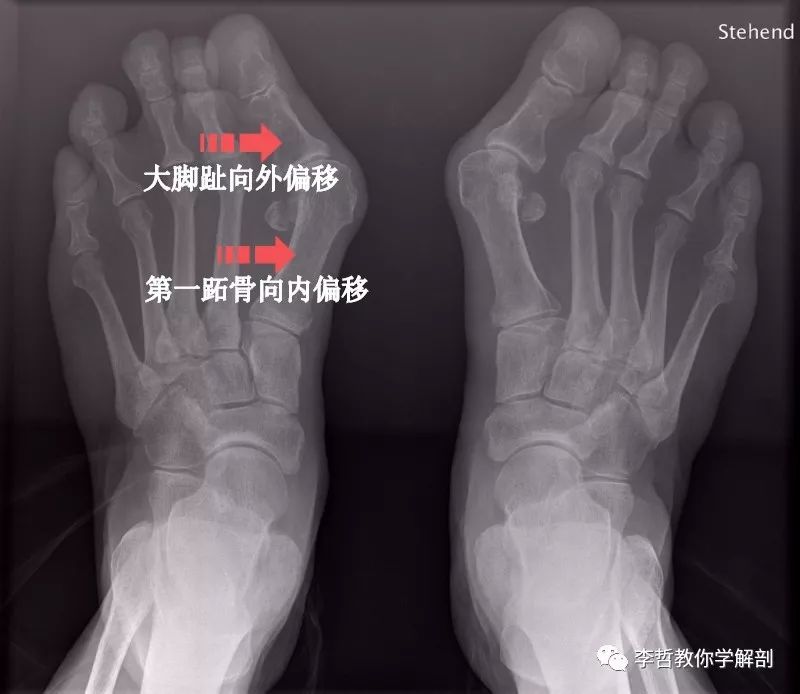

拇外翻是指大拇趾向外侧偏移和旋转,跖骨向内。

当拇指外翻达至某一个程度时,他的力就会影响他的邻居第一跖骨。第一跖骨就会向内侧移或呈内翻,导致前脚掌的宽度增加。穿着鞋子时,第一跖骨内侧的韧带与鞋摩擦,局部的软组织发炎,关节囊变肿胀引起疼痛。